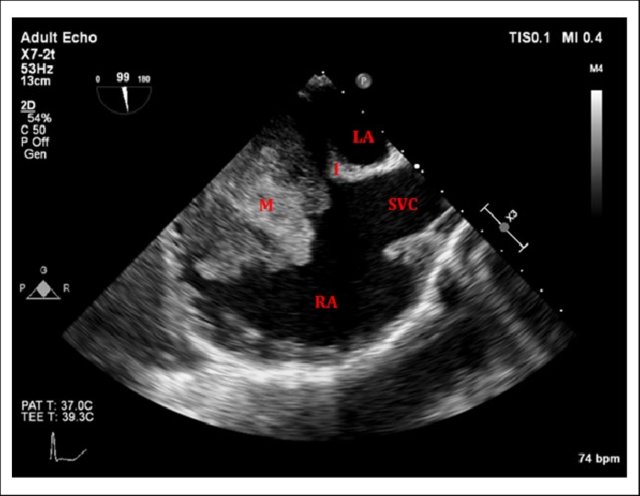

RA myxoma attached to septum: Image source -Michael Essandoh from Research gate

Cardiac myxoma is the most common primary tumor of the heart that presents as mitral inflow obstruction/ regurgitation often with a systemic presentation. It can be either familial, syndromic, or sporadic. Excellent imaging is possible and diagnosis has become straightforward. Surgery is the specific treatment,

What information do the Surgeons need?

Size, attachment to surrounding structures is the key. The myxoma origins most often in IAS and defining its attachment is crucial. Mitral leaflet distortion, Injury ( and even attachment) is possible. It is helpful for the surgeons if we let them know the mechanism of mitral regurgitation prior to surgery. Echocardiogram including TEE is sufficient in most. MRI may add some more info. The aim of surgery is to remove the tumor mass completely.

Note 50 % tumor mass enters the left ventricle with diastole. No wonder, as the tumor plops with diastolic cardiac cycle a high-pitched sound simulating opening snap followed by an MDM perfectly mimics rheumatic mitral stenosis. An MR murmur is equally common.

4 chamber view showing what appears to be a small narrow pedicle attaching to IAS. Please note echo imaging can be deceiving. Surgeons must inspect the mass in toto before taking the decision to excise IAS or not

TEE imaging of LA myxoma. Note how fragile the edges of the tumor looks. It explains the high incidence of tumor embolus in this condition. Also, to be noted is the forceful impact of the tumor mass on AML that predisposes chronic mitral valve damage.